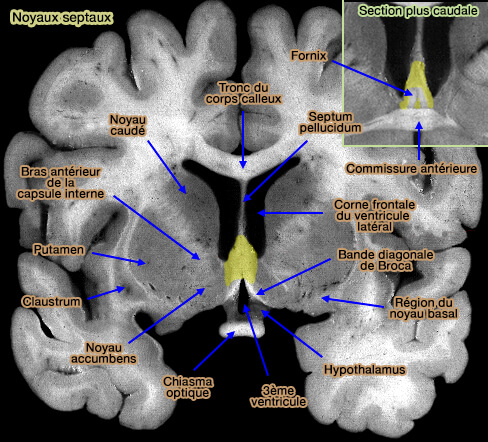

Septum : noyaux septaux

Les noyaux septaux sont situés dans le cerveau antérieur basal et contigu au septum pellucidum.

Ils se répartissent verticalement en quatre groupes bien visibles chez les insectivores, mais plus flous chez l'homme et sont souvent hétérogènes et comprennent plusieurs noyaux ou sous-noyaux.